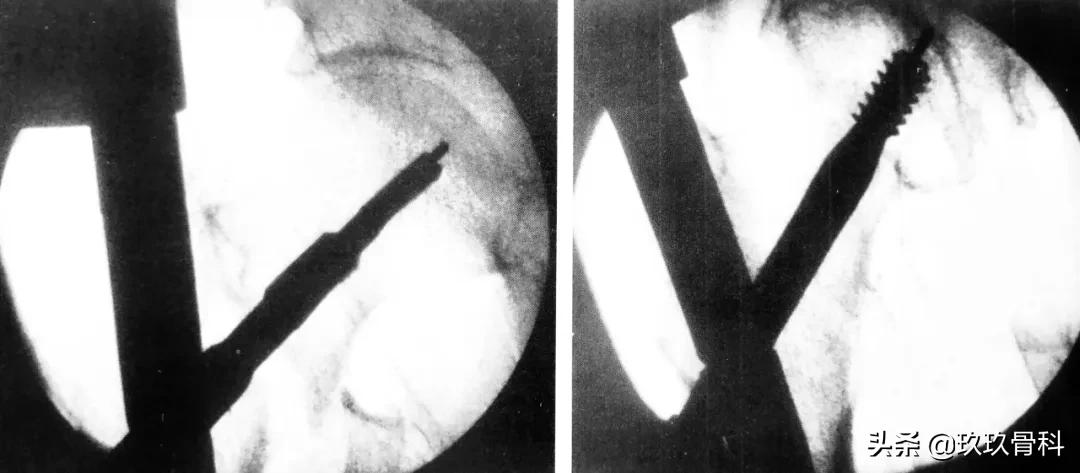

拉力螺钉的正确放置非常重要,其前提是首先安放好导针的位置,即正位必须与股骨颈轴线重叠或位其稍下方,侧位或斜位导针应在股骨颈中心。

A 拉力螺钉的安装;B 拉力螺钉的正确位置

拉力螺钉的置入,A 确定长度;B 阶梯钻钻孔 C 拧入拉力螺钉并加压

阶梯钻钻孔、正位拉力钉位置

侧位拉力钉位置、远端锁钉置入